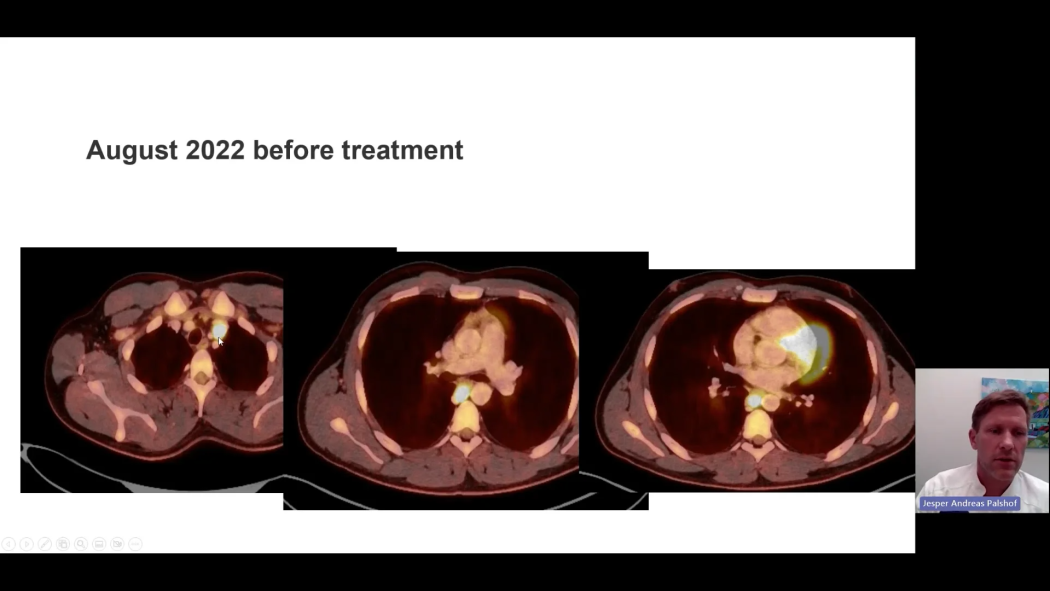

Case experiences with combination therapy with cabozantinib + nivolumab as first-line treatment